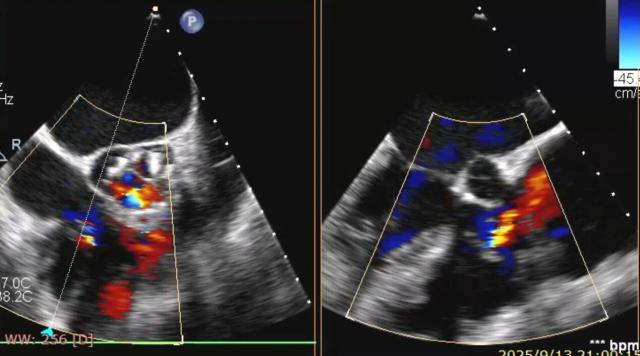

術(shù)后食道超聲顯示反流情況明顯好轉(zhuǎn)。

手術(shù)當(dāng)天,術(shù)前心臟超聲及CTA檢查發(fā)現(xiàn),患者三尖瓣環(huán)擴(kuò)大明顯,反流位置復(fù)雜。手術(shù)團(tuán)隊(duì)依據(jù)影像結(jié)果精準(zhǔn)規(guī)劃,分別在后瓣環(huán)及前、后瓣環(huán)處植入兩枚K - Clip夾合裝置,如同在心臟的后背“門(mén)框”和前后交界各夾一枚“夾子”,增強(qiáng)瓣葉對(duì)合。術(shù)中,患者血流動(dòng)力學(xué)穩(wěn)定,手術(shù)順利完成。術(shù)后即時(shí)評(píng)估顯示,患者心臟從原來(lái)的“大漏水”變?yōu)椤拜p微滲水”,喘和腫的癥狀也明顯減輕。手術(shù)效果顯著,患者癥狀迅速緩解。